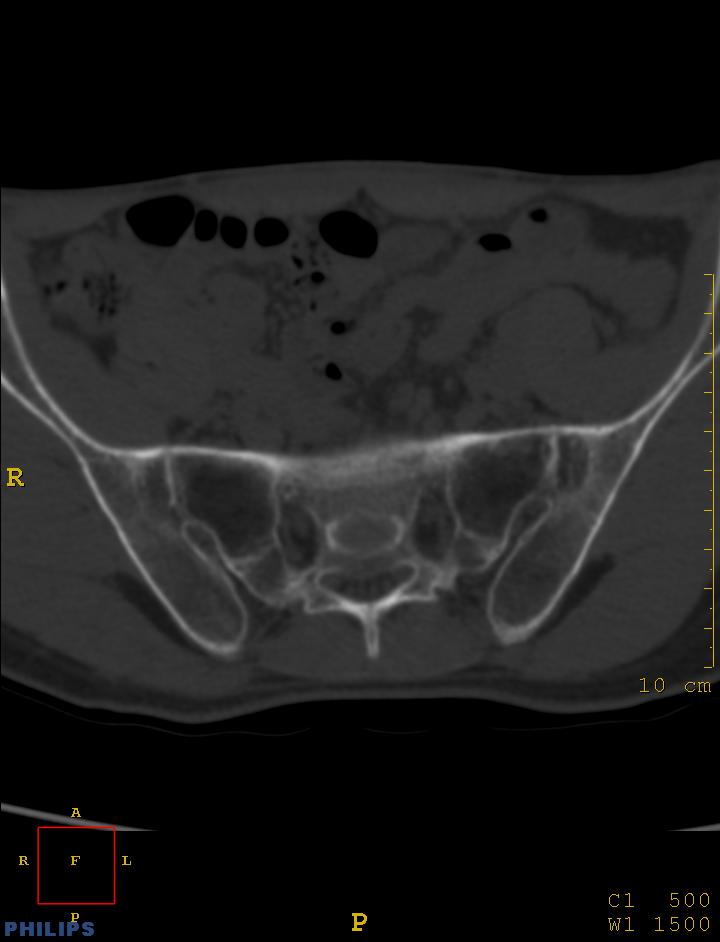

标题: CT14032:M34Y,双侧骶髂关节

m,34岁,腰痛三年,腰椎活动度明显减低,x片示腰椎竹节样改变

双侧骶髂关节面融合;强直脊柱炎

双侧骶髂关节骨性融合,软骨下囊性变,结合脊柱竹节样改变,典型的强直性脊柱炎。